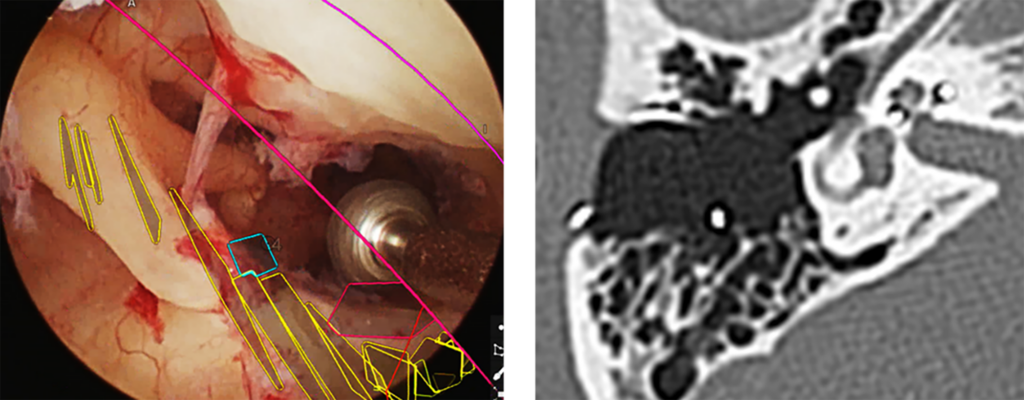

近年、難聴が認知症のリスクとして最も関連が深い因子であるとの報告がなされ、日本でも難聴対策がクローズアップされています。当科では補聴器外来を開設し、補聴器を使いこなすための取り組みを行っております。補聴器での効果が乏しい方には、人工聴覚器(人工中耳・人工内耳)での聴力の再獲得に取り組んでいます。特に人工内耳手術は、約2~3㎝の皮膚切開で安全に、短期間の入院で可能な、拡張現実型(AR)ナビゲーションを用いた画像誘導内視鏡下人工内耳植込術を開発し、施行しています(図5)。